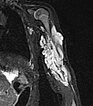

Zur weiteren Sicherung der Differentialdiagnose wird bei dem Kind auch eine MRT durchgeführt. Hier abgebildet eine koronare, T2-gewichtete, fettunterdrückte STIR-Sequenz. Der Tumor ist hier stark hyperintens (weiß im Bild) und scharf zum umgebenden Gewebe abgegrenzt. Er durchdringt alle Gewebeebenen und enthält zentral als Zeichen einer starken arteriellen Perfusion signalfreie Areale, sogenannte Flow-voids.